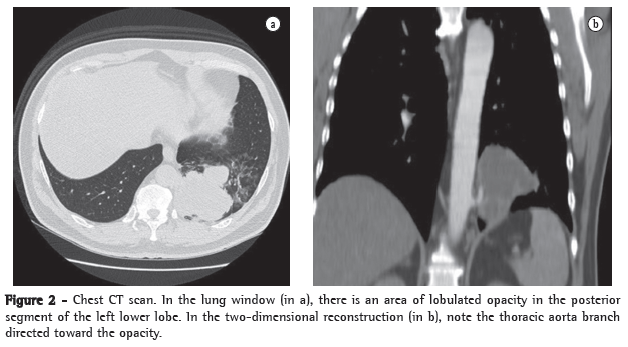

Physical examination revealed good general health, no fever, an HR of 88 bpm and an arterial pressure of 90-145 mmHg. The cardiac auscultation was normal, and examination of the lung revealed reduced expansion and diminished breath sounds in the lower third of the left hemithorax, as well as dullness to percussion in this same region. The rest of the physical examination revealed no abnormalities. The results of the laboratory tests performed at admission, such as blood workup, lipid profile, coagulation profile, determination of electrolyte concentrations, renal function test and hepatic function test, were normal. The ESR was 32 mm/h. Serology for HIV was negative. A chest X-ray at admission revealed opacity in the posterior segment of the left lower lobe (Figure 1). A CT scan of the chest with two-dimensional reconstruction revealed an aortic branch directed toward the pulmonary opacity (Figure 2), which is consistent with a diagnosis of pulmonary sequestration. The patient was referred for surgery, and a left lower lobectomy was performed to resect the anomalous pulmonary tissue (Figure 3). After the macroscopic analysis of the surgical sample, the patient was diagnosed with intralobar sequestration. The postoperative evolution was favorable, and the patient was discharged to outpatient treatment.

In the investigation of a suspected case of pulmonary sequestration, imaging studies have two principal objectives: to rule out other pathologies; and to confirm the presence of an anomalous arterial supply.(12-15) The most common radiological presentation is a ­homogeneous opacity in the posterior basal segment of the left lower lobe. Arteriography allows the characterization of anomalous arteries, providing valuable information for preoperative planning.(13) Similarly to nuclear magnetic ­resonance imaging, spiral CT allows the visualization of the source and course of the vessels in most cases. In such cases, angiography is unnecessary.(10,15) The diagnosis of pulmonary sequestration is confirmed by multichannel CT scans of the chest with intravenous contrast and reconstruction, there being no need for aortography or magnetic resonance imaging of the chest and abdomen, since CT scans of the chest and upper abdomen allows the visualization of the arterial vessel communicating with the sequestration and of the changes in the lung parenchyma.(14,15)

In this report, the patient reported two previous episodes of massive hemoptysis one week earlier and had an area of opacity behind the cardiac silhouette in the left base. The patient had no weight loss, and his overall health status was preserved-data that argued against a neoplastic etiology. The patient reported no history of comorbidities or recurrent infections. He was admitted for diagnostic investigation. Chest CT scans with intravenous contrast and two-dimensional reconstruction revealed pulmonary sequestration with individualization of the anomalous arterial supply. The patient underwent surgery, in which the anomalous pulmonary tissue was resected, and, after the macroscopic analysis of the sample, was diagnosed with intralobar sequestration. The case presented here is rare. The postoperative evolution was favorable, and the patient was discharged to outpatient treatment.